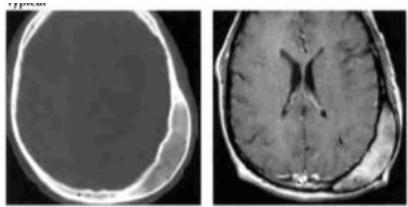

Analise as imagens abaixo.

Fonte: OSBORN, 2004.

As imagens acima são típicas de: